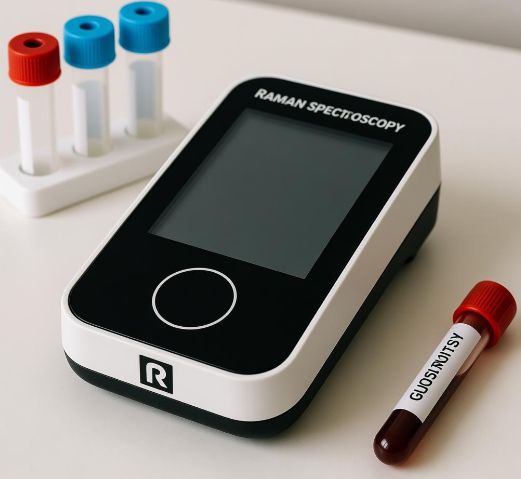

基于拉曼光谱的血糖监测仪

一、引言基于拉曼光谱的血糖监测仪是一类近年来备受瞩目的非侵入式血糖监测设备,它利用光谱学原理在皮肤表面检测血糖分子的特征拉曼指纹信号,从而实现血糖浓度的推断。由于糖尿病患者需要长期、频繁地监测血糖水平,因此非侵入式、无痛化、可连续实时监护的技术路线成为全球医学工程领域的重要突破方向。传统的血糖监测依赖指尖采血或采用皮下植入式传感器,存在疼......